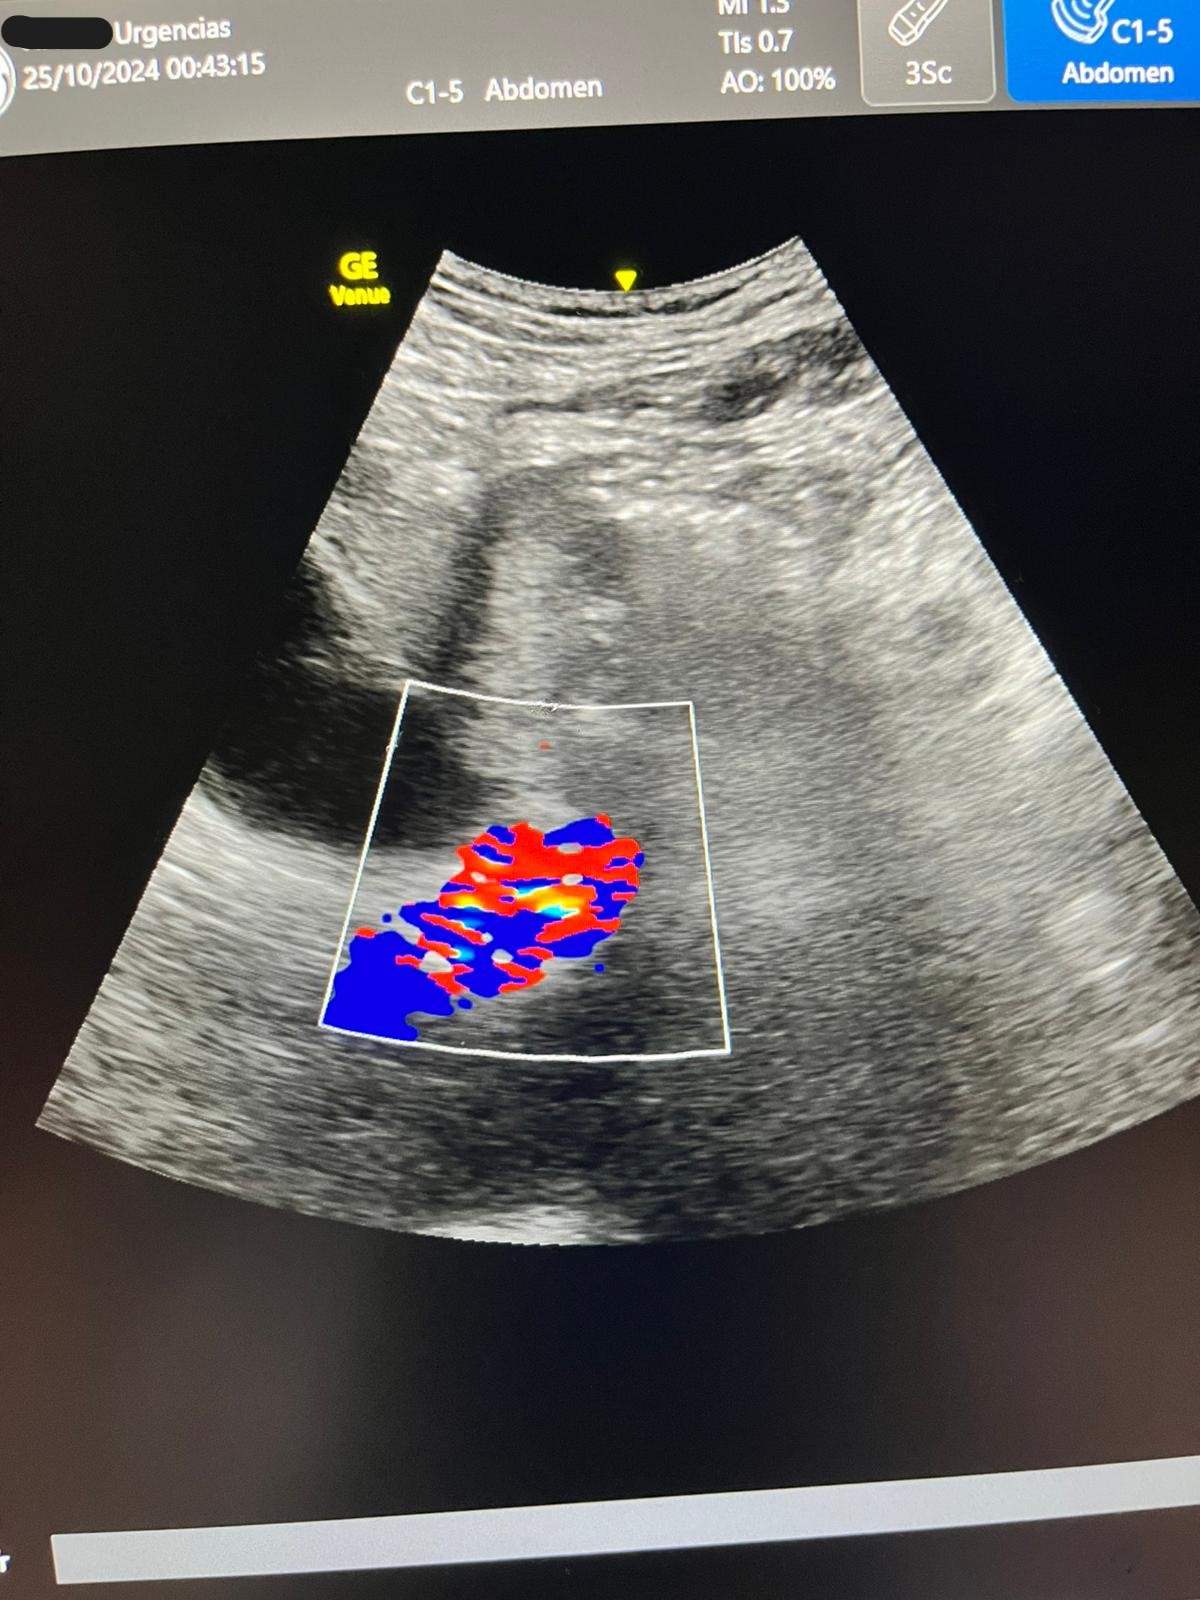

Ecografía: hígado y vías biliares normales sin formaciones expansivas. Coledoco de calibre normal.

Vesícula biliar distendida con litiasis múltiple suncentimétricas y barro biliar de paredes finas.

JC: coledocolitiasis DxD: IAM, cólico biliar.